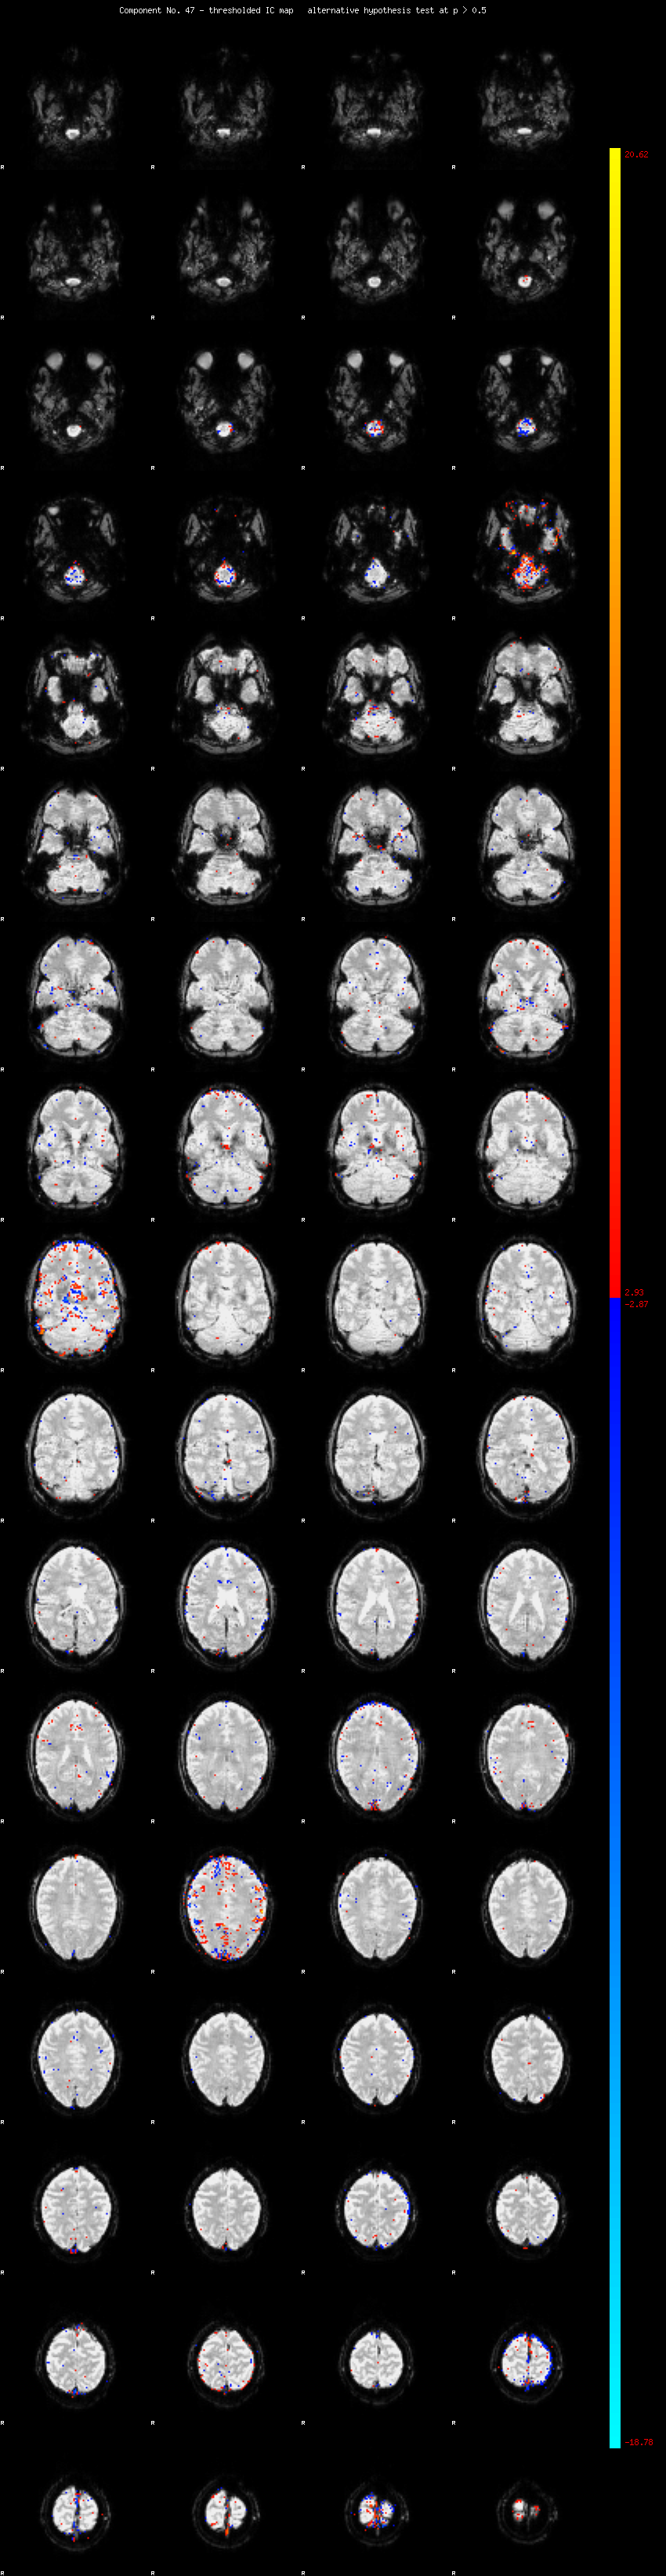

MELODIC Component 47

1.02 % of explained variance;     0.68 % of total variance